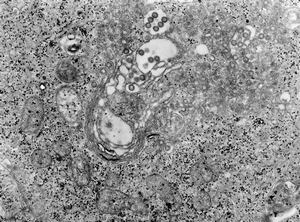

ビーブラスト (B-blast) 鳥類用マルチビタミン120ml スナノミ症(Tungiasis) ~ スナノミがヤギの皮膚に侵入して埋没することで起こる寄生虫症 ヤギ(山羊)の病気 X Facebook はてブ LINE Pinterest コピー 2021.03.02 スナノミ症は、ツンガ属:Tunga属(ノミ目:Siphonaptera:シフォナプテラ)のメスのスナノミがヤギの皮膚に侵入して埋没することで起こる寄生虫症です。 2015年、ウガンダでは子山羊に発生したスナノミ症の重症例が2件ありました。 目次 症状治療予防 症状 ●皮膚病変 治療 ※支持療法 予防 ※防虫剤を使用する。 ブックマークに追加